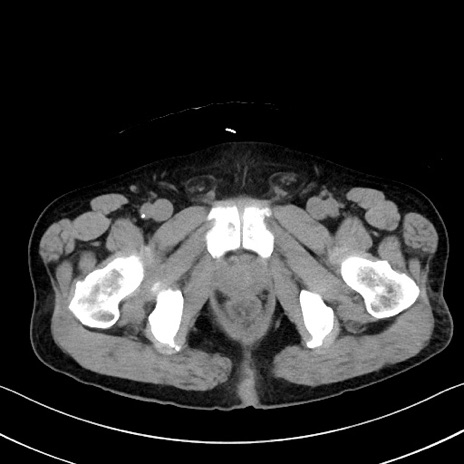

症例35(横断像)

【症例】70歳代 男性

【主訴】腹部膨満、嘔吐

【現病歴】昨日より腹部膨満感出現。本日増悪し、仙痛出現。嘔吐あり、受診。

【既往歴】糖尿病、胆摘後

【身体所見】BP 149/80mmHg、HR 74/min、BT 35.9℃、腹部:膨満、軟、圧痛なし。腸雑音減弱あり。上腹部正中切開瘢痕あり。

【データ】WBC 13500、CRP 1.72